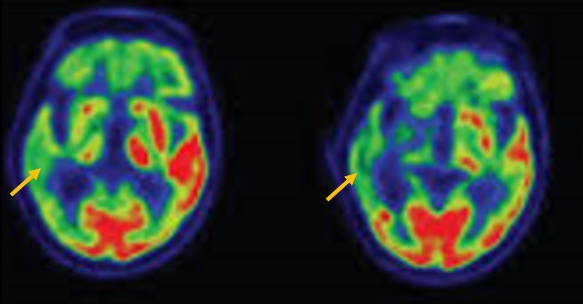

다계통 위축이란 뇌의 다양한 계통에서 위축이 발생하는 것을 의미합니다. 파킨슨 증상이 있으면서 질병 초기에 소변 장애나 기립성 저혈압으로 인한 어지러움이 두드러지게 나타나는 경우, 보행 시 비틀거림이나 구음 장애와 같은 소뇌 위축에 따른 운동 실조 증상이 나타나는 경우, 꿈에서 하는 행동을 수면 중에 보이는 렘수면 행동 장애가 동반되는 경우 다계통 위축을 의심합니다. 다계통 위축은 파킨슨병과 달리 안정 시 떨림이 잘 보이지 않고, 증상이 대칭적인 경우가 많으며, 진행이 빠르며, 레보도파와 같은 항파킨슨 약제에 잘 반응하지 않습니다. 다계통 위축은 뇌 자기공명영상(MRI)에서 교뇌에 십자 모양의 고음영이 나타날 수 있는데, 이를 십자무늬 빵(hot cross bun) 징후라고 합니다. 또한 초기에서는 뇌 자기공명영상(MRI)이 정상으로 보이더라도 뇌포도당 양전자 단층촬영(PET)에서는 소뇌 또는 기저핵의 대사 기능이 저하된 상태가 관찰될 수 있습니다. 이러한 영상 소견은 특징적인 임상 증상과 함께 진단에 참고할 수 있습니다.

[다계통위축 환자의 뇌자기공명영상에서 확인되는 십자무늬빵 징후]

[다계통위축 환자의 뇌포도당 양전자 단층 촬영에서 확인되는 소뇌의 대사 기능 저하]